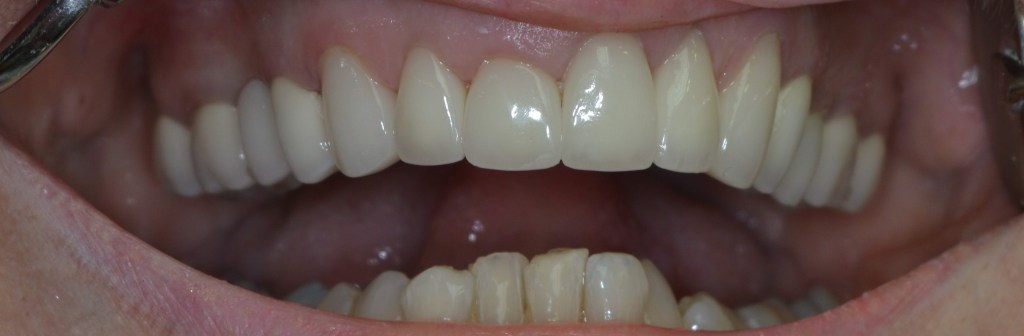

Kozmetikai és funkcionális kezelés: felső torlódott fogak kiegyenesítése, koronák enyhe kifele döntése, mélyharapás korrigálása.

A választott korona típusa: CAD/CAM (komputer vezérelt tervezés/megmunkálás) technológiával készült cirkónium (fémmentes) szóló koronák.

A választott fogszín: A2

A protetikai munka elkészülésének ideje: 5 munkanap.